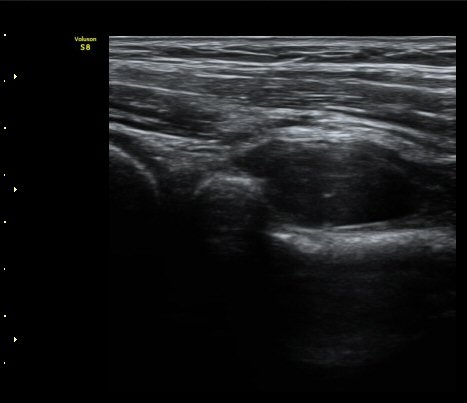

ŽÃËÀÚ¸¦ Á» ´õ ¸»´ÜÀ¸·Î À̵¿ÇÏ´Ï ³¶Á¾Àº ´õ Å©°Ô °üÂûµÈ´Ù(±×¸² 3, 4).

¿ä°ñÀ» Á¾´Ü¸éÀ¸·Î °üÂûÇÏ´Ï ¿ä°ñ ±ÙÀ§ºÎ Ç¥Ãþ¿¡ ³¶Á¾ÀÌ È®Àεǰí(±×¸² 5) ŽÃËÀÚ¸¦

Á¶ÀýÇÏ´Ï Èİñ°ß½Å°æÀÇ Á¾´Ü¸é À̹ÌÁö°¡ °üÂûµÇ´Âµ¥ ³¶Á¾¿¡ ÀÇÇØ Ç¥ÃþÀ¸·Î ÀüÀ§µÇ¾î